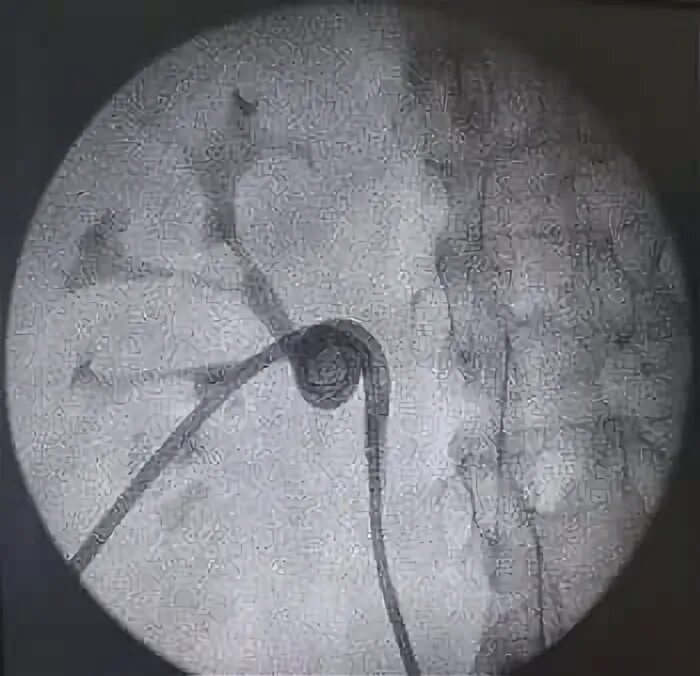

Литотрипсия желчных камней